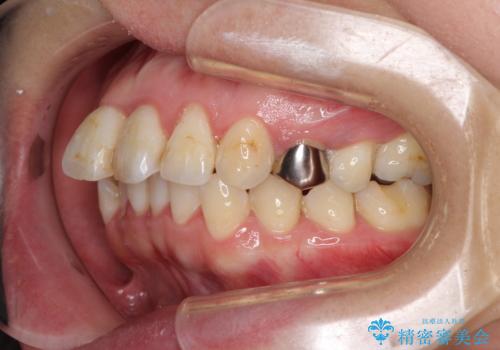

- 出っ歯と口の閉じにくさ、デコボコを気にして来院された患者様です。

口元の突出感を改善するため、上下左右第一小臼歯4本の抜歯を行い、ワイヤー装置による矯正治療を行うこととしました。

上下前歯の距離が大きかったため、上下の歯が接触するまでに時間がかかりました。

それでも目安である2年半で終えることができ、患者様には大変満足していただけました。